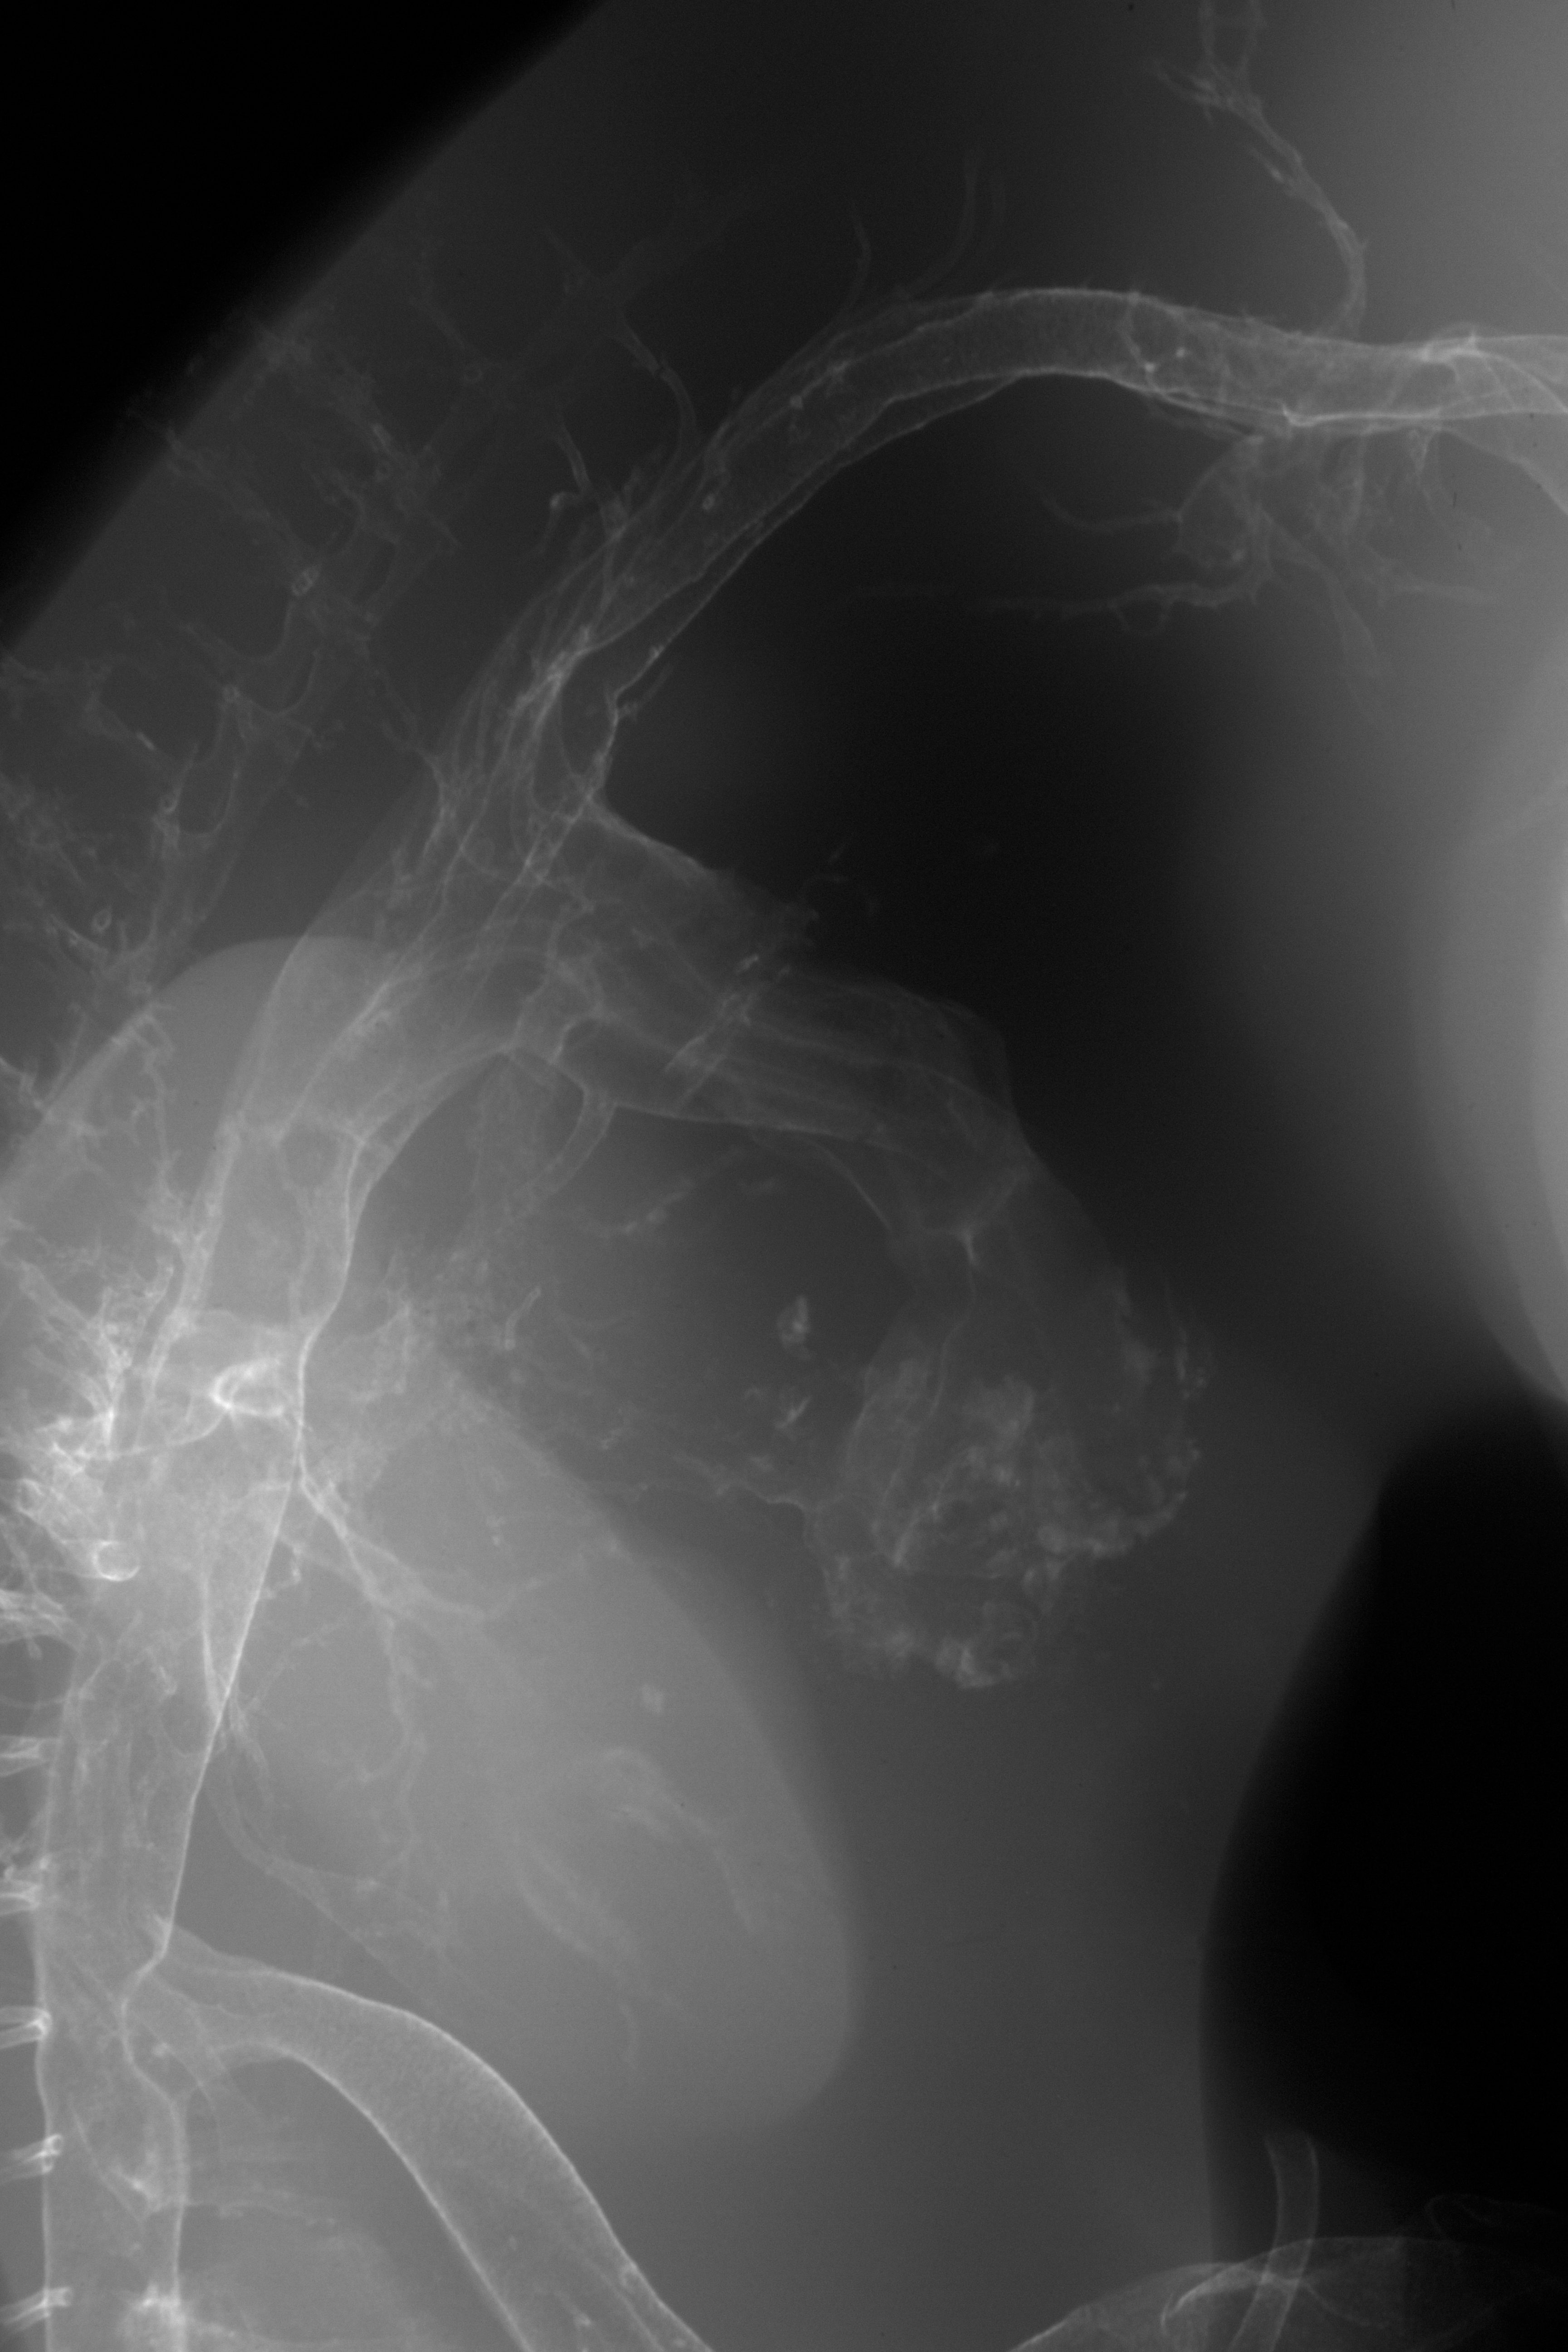

Chick Embryo Microangiography

Hamburger-Hamilton (HH) Stage 29 (approx. 6 - 6.5 days)

Stereo X-Ray Micrographs